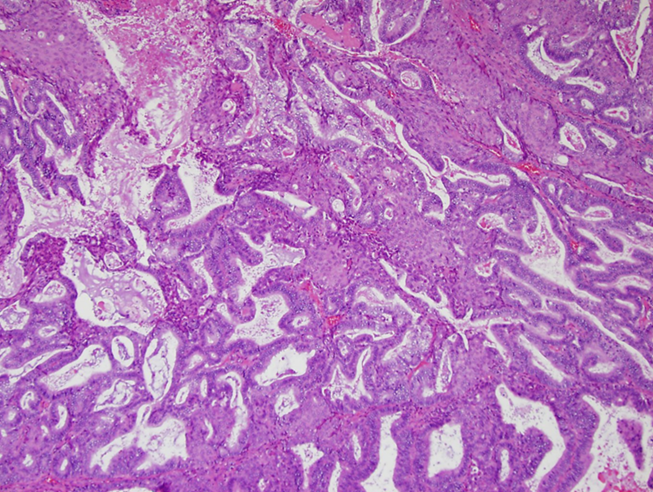

Mucinous Borderline Tumors are cysts with proliferation of the epithelium and complex architecture

→ is non-invasive